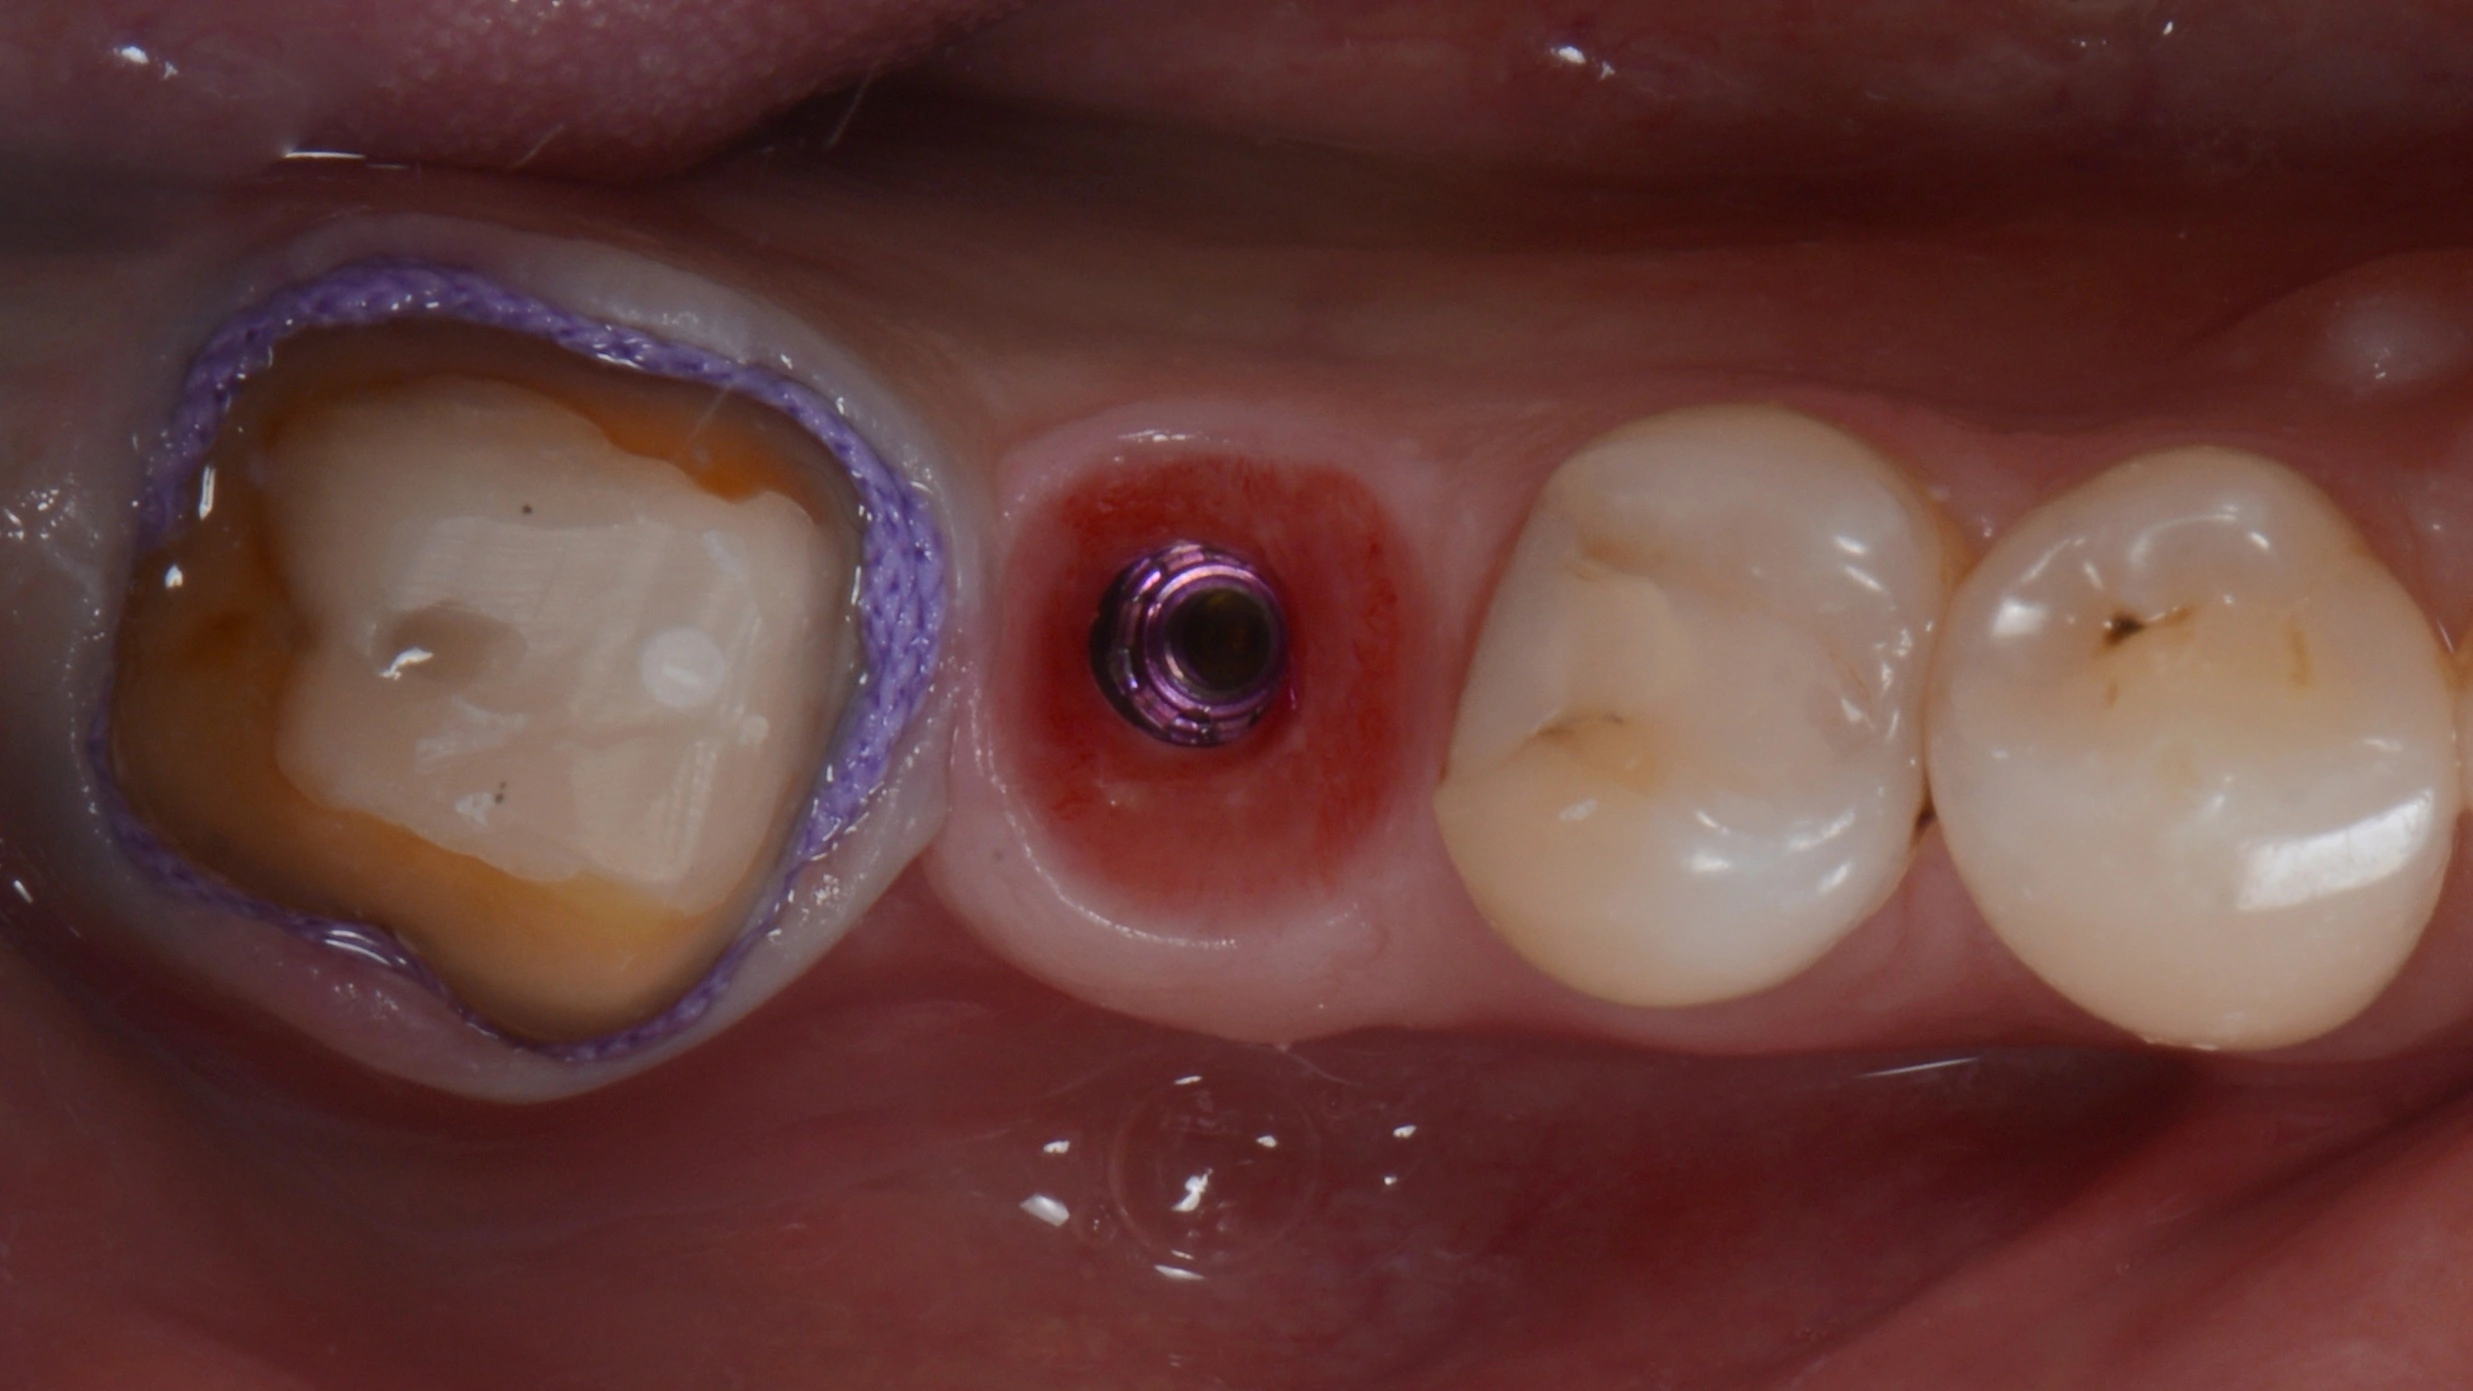

В данном кейсе не стали прибегать к ортодонтическому лечению, а просто установили имплантат MIS С1

Далее провизорное протезирование с препарированием зуба 47, и после формирования профиля постоянное протеизрование коронками на цементной фиксации на имплантате и на зубе. Зачастую, не всегда вижу необходимость в апрайте семерок, особенно, если в дальнейшем их еще и требуется покрыть коронкой.